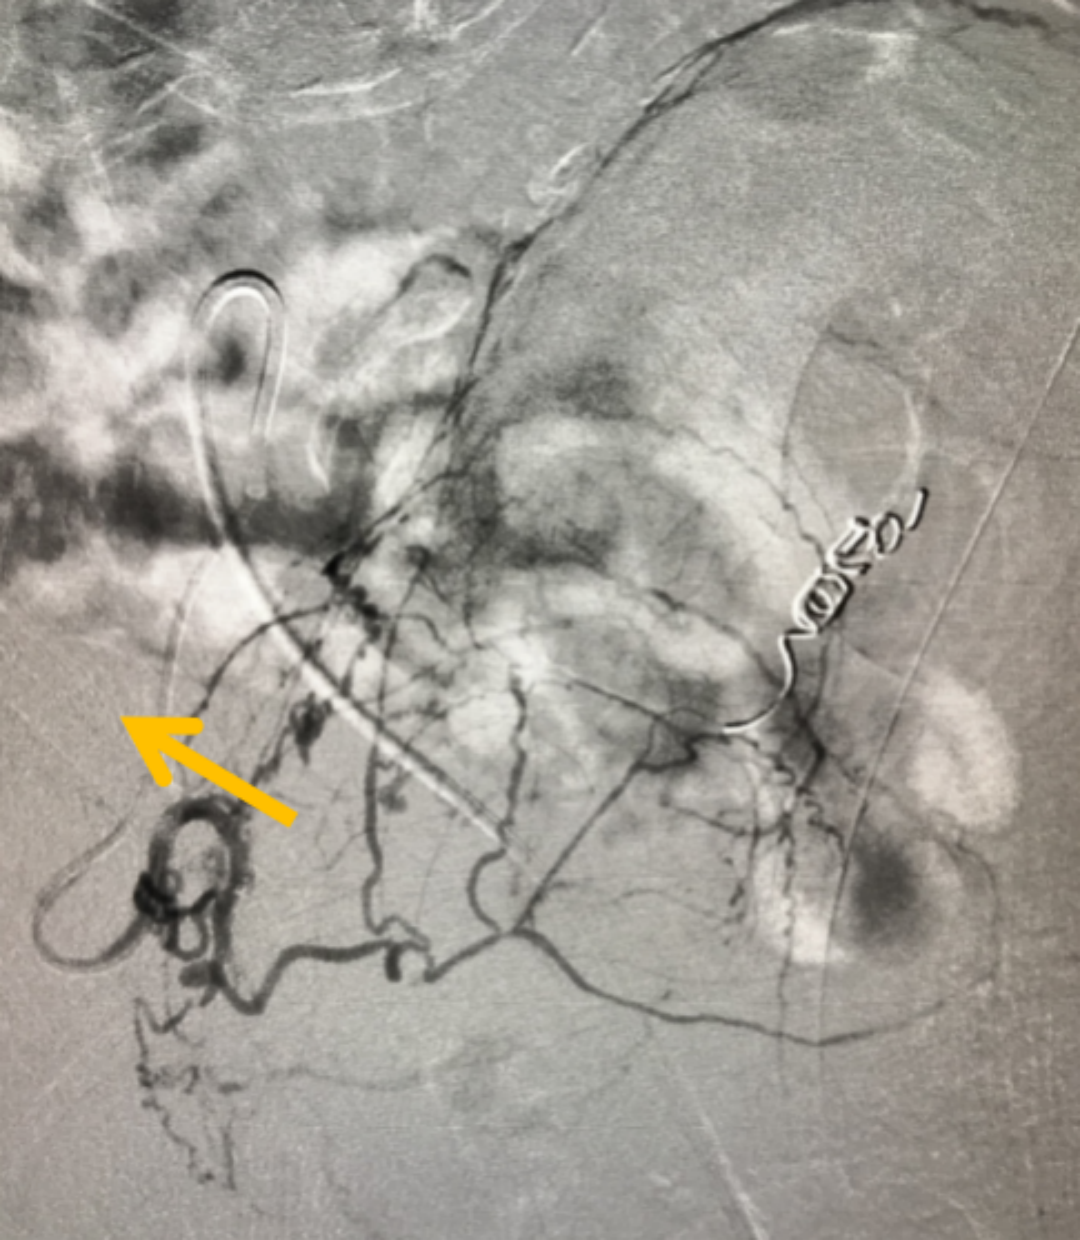

在全面评估后,团队为他制定了PAE的精准治疗方案。手术仅通过大腿根部一个针眼大小的穿刺点,将比头发丝还细的微导管,在影像引导下精准送入供养前列腺的动脉,并注入安全的栓塞微粒。这个过程,就像精准地“断粮”

图:微导管(箭头所指)

增生的前列腺组织需要充足的血液供应才能维持“生长”。PAE技术的核心,就是阻断这些供给增生的“营养通道”,从而让过度增殖的组织因“饥饿”而自然萎缩、坏死,解除对尿道的压迫。

图:使用CBCT扫描避免误栓其他血管